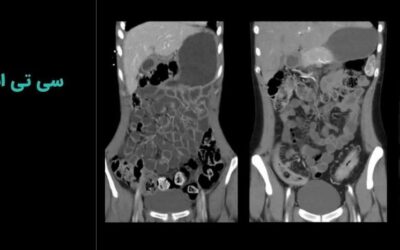

در این روش با استفاده از دستگاههایی مانند پت اسکن، سی تی اسکن و ام آر آی، نمایی سه بعدی از تومور و بافتهای اطراف آن بهدست میآید. براساس این تصاویر، محل، اندازه و شکل تومور بهطور دقیق مشخص میشوند.

این بیمارستان فوق تخصصی بهعنوان یک مرکز تصویربرداری سرطان از جدیدترین تجهیزات تصویربرداری مانند سی تی اسکن و MRI پیشرفته با قابلیت تصویربرداری سه بعدی و کادر درمانی مجرب بهره میبرد.